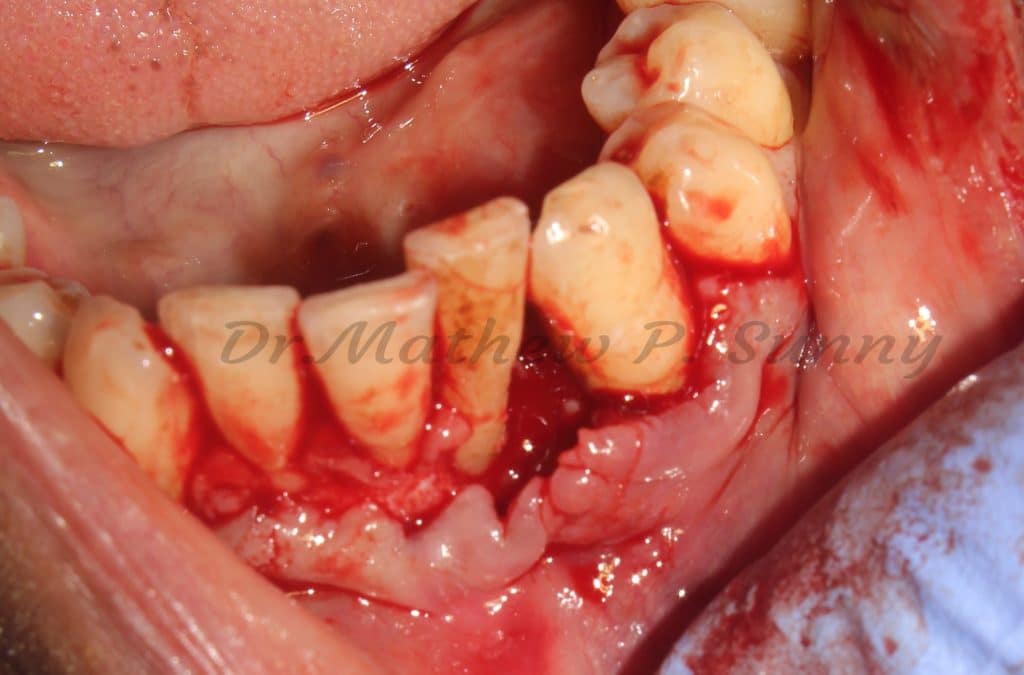

Scaling was followed by flap elevation, removal of granulation tissue and most importantly.. all subgingival calculus.

flap raised..

bone defect noted.. and all granulation tissue curreted..

subgingival calculus is noted and then removed..